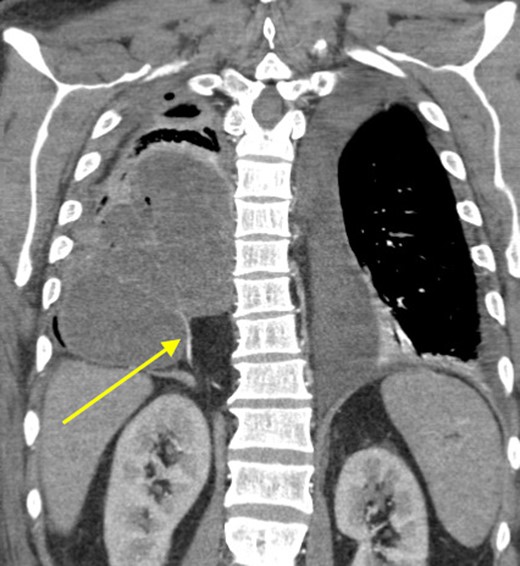

At that time, we started to wonder if this patient had ILPS, which prompted us to scrutinize his prior CT scans. Surprisingly, we noticed an anomalous arterial supply from the right renal artery that traversed through his Bochdalek hernia and into the sequestration (Figs 2 and 3). Two days after the operation, the patient was extubated and his clinical course was relatively benign. Also, no pathogens were detected by microbiological analysis of the intraoperative cultures and bronchial lavage. Pleual biopsies from the first operation just showed some acute fibrinous pleuritis with calcium. One week later, his mental status recovered at baseline, he was breathing without supplemental oxygen and his WBCs count had normalized. The patient was discharged to rehab with follow up in the clinic to discuss surgical resection of the ILPS in order to prevent recurrent symptoms.

Sagittal view showing anomalous bloody supply originating from proximal right renal artery.